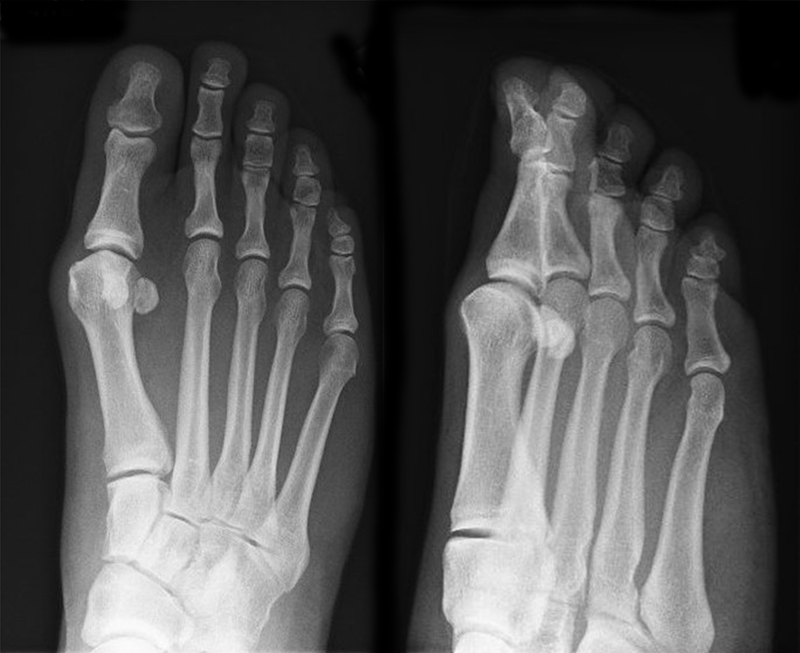

• Die Operationsplanung erfolgt anhand der Röntgenaufnahmen des Vorfußes unter Belastung in 2 Ebenen. Für die Verfahrenswahl sind wichtig der Intermetatarsalwinkel und die Breite des Os metatarsale, der Hallux valgus Winkel, der distalen Gelenkflächenwinkels (Distal Metatarsal Articular Angulation - DMAA), des Metatarsaleindex und Sesambeinposition (Abb. 1).

• Röntgenkontrollen (Vorfuß d.p. und seitlich) postoperativ ohne Belastung. Weitere Kontrollen erfolgen 6 Wochen, sowie 3, 6 und 12 Monate jeweils unter Belastung.